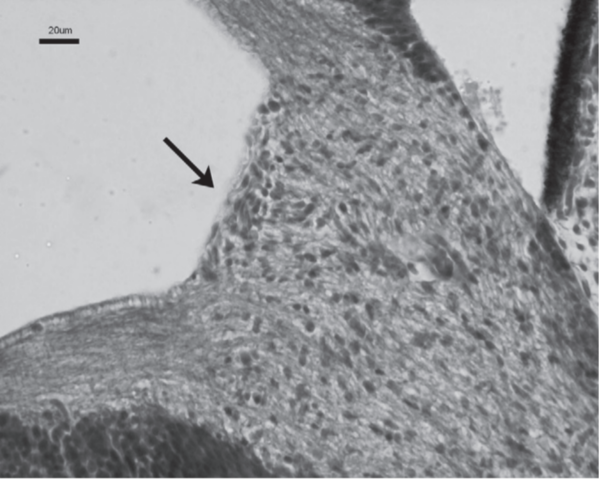

Al final del período embrionario, el nervio

óptico presenta un trayecto que va desde la parte posterior del globo ocular hasta el quiasma. Los glioblastos se acumulan en la papila, separan las fibras nerviosas en la

región coroidea, forman una limitante precisa y en el trayecto infraorbitario, separándolo del mesénquima

vecino (esbozo del manto periférico de Greef).

La retina muestra positividad entre

las semanas 8 y 10, quedando la positividad restringida después de la semana 21 a la capa de células ganglionar y

a la capa nuclear interna.